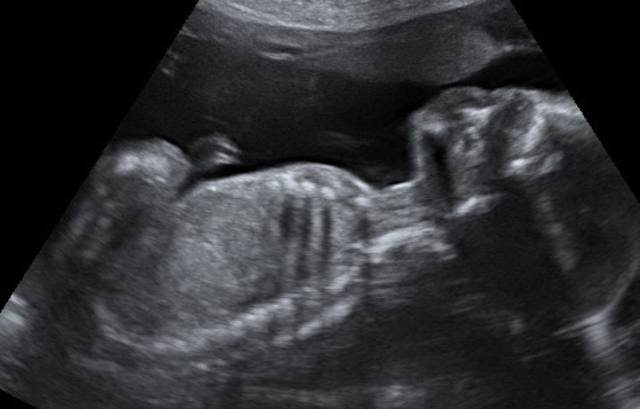

• novena semana

novena semana

El embrión mide entre 2 y 3 centímetros, su forma ya es mucho mas parecida a un ser humano. Las piernas se alargan, aparecen las manos,, se observa el tuberculo genital que va a denterminar los genitales femeninos o masculinos.